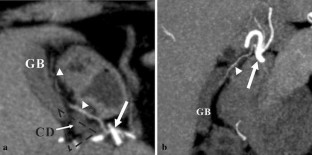

Assessment and classification of cystic arteries with 64-detector row computed tomography before laparoscopic cholecystectomy

Major complications of laparoscopic cholecystectomy are bleeding and bile duct injury, and it is necessary to clearly identify structures endoscopically to keep bleeding and injury from occurring. The aim of this study was to depict the anatomical variation between cystic arteries among patients using 64-detector row spiral computed tomography (CT) prior to laparoscopic cholecystectomy.

A total of 78 patients (31 men, 47 women) who underwent cholecystectomy were examined preoperatively using 64-detector row spiral CT between April 2012 and June 2013. The origin and number of cystic arteries and their relationship with the Calot triangle was evaluated by two independent observers. CT images were compared with laparoscopic cholecystectomy results.

The cystic arteries were delineated by CT in 73 of the 78 patients. The relationship between the cystic arteries and the Calot triangle was identified in 71 of the 78 patients. One cystic artery was found in 53 (73 %) of the 73 patients, while two cystic arteries were found in 20 (27 %) of the patients. A total of 55 (60 %) of the 91 cystic arteries passed through the Calot triangle. The remaining 36 cystic arteries (40 %) passed anterior, posterior, or inferior to the cystic duct. The relationship between the cystic arteries and the Calot triangle detected by CT was in agreement with the surgical records for all patients.

The configuration of the cystic arteries and their relationship with the Calot triangle can be identified using 64-detector row CT before laparoscopic cholecystectomy.

Fig. 2